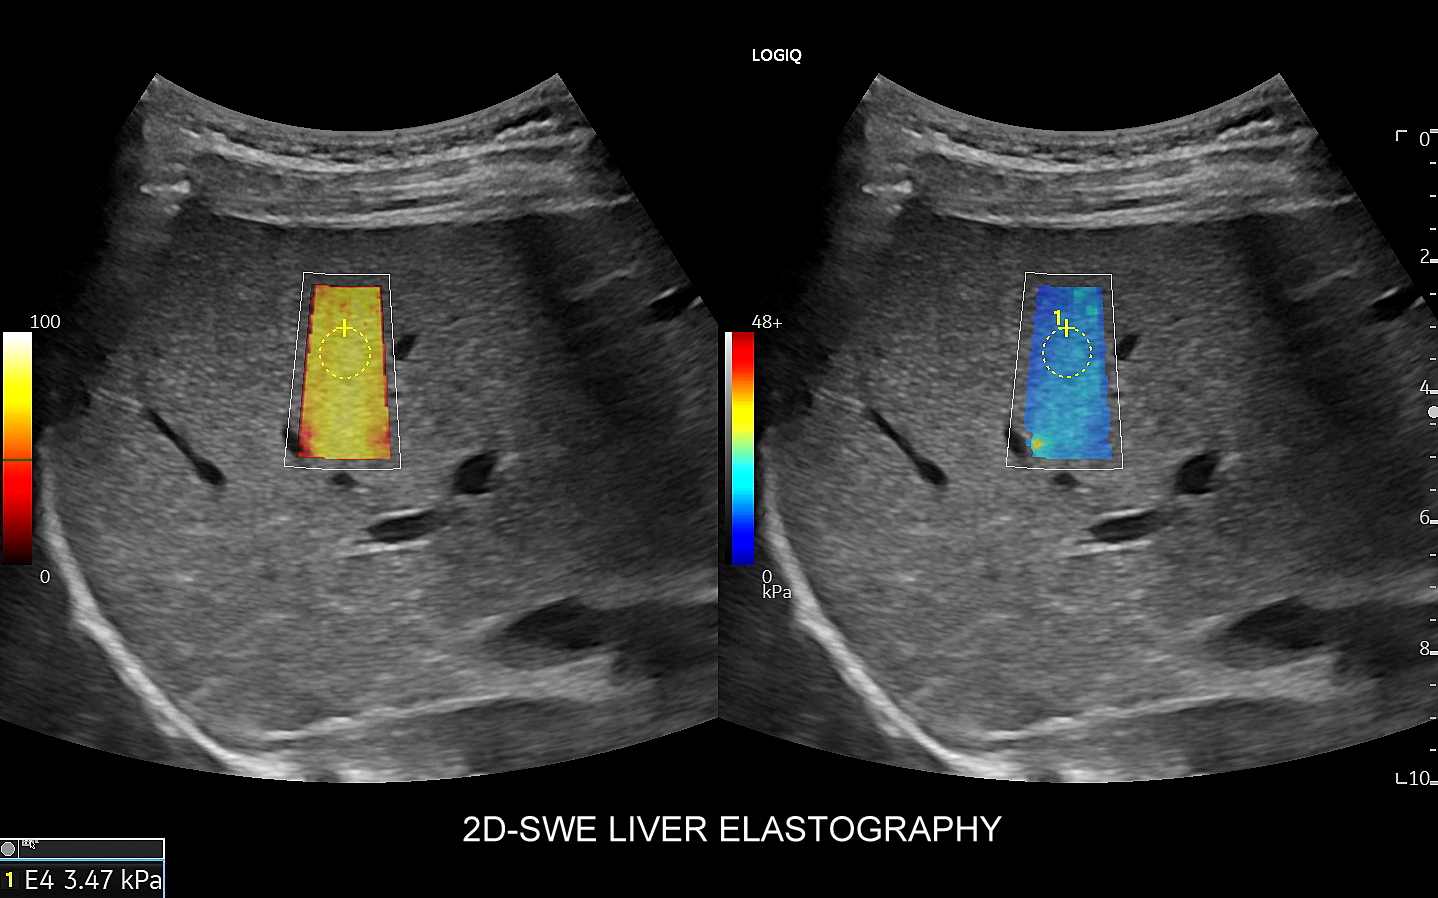

Elastografia jest metodą diagnostyczną oceniającą sztywność i spoistość tkanek. Istnieje kilka rodzajów technik elastograficznych. W przypadku badania miąższu wątroby wykorzystuje się technologię opartą o prędkość rozchodzenia się fali poprzecznej pod wpływem zastosowania impulsu mechanicznego. Otóż im tkanka jest sztywniejsza tym wyższa jest prędkość rozchodzenia się fali. Opisaną metodę określa się jako shear wave imaging (SWI).

Na przestrzeni czasu metoda SWI ulegała ewolucji. Jej starsza odmiana to tzw. Fibroscan, który jest badaniem „na ślepo”, gdyż nie umożliwia precyzyjnego wyboru miejsca oceny miąższu wątroby. Odmianą najnowszą i wysoce precyzyjną jest elastografia 2D-SWE (2D sheer wave elastography). W badaniu 2D-SWE możliwy jest wybór konkretnego miejsca pomiaru w obrębie wątroby; dodatkowo generowana jest mapa kodowaną kolorem odpowiadająca mnogim punktom pomiaru, które następnie w trakcie post-processingu można wybrać w celu uzyskania dokładnego i wiarygodnego wyniku.

W jakim celu wykonywana jest elastografia wątroby? Elastografia 2D-SWE precyzyjnie ocenia sztywność miąższu wątroby, która to wzrasta w procesie włóknienia na tle przewlekłych schorzeń narządu, np. zapaleń. Badanie pozwala w ten sposób ocenić stopień zaawansowania zwłóknienia lub marskości wątroby. Dokładność oszacowania zwłóknienia w elastografii 2D-swe jest na tyle precyzyjna, iż zastępuje ona w omawianym wskazaniu medycznym biopsję wątroby.